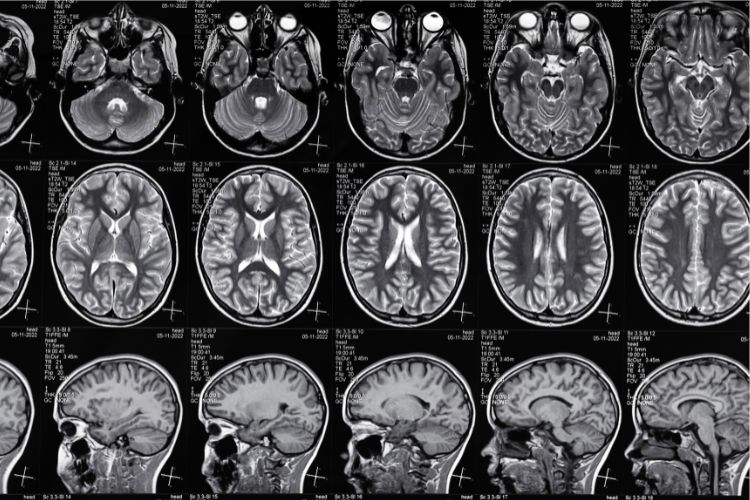

MR koristi magnetno polje i radio talase za detaljne slike tela, bez zračenja. Traje 30-60 minuta i efikasna je za otkrivanje anomalija mozga, tumora, srčanih problema i više.

Magnetna rezonanca glave je bezbolna i detaljna metoda snimanja mozga, koristi se za dijagnostiku neuroloških tegoba. Priprema je jednostavna, a rezultati brzo dostupni.